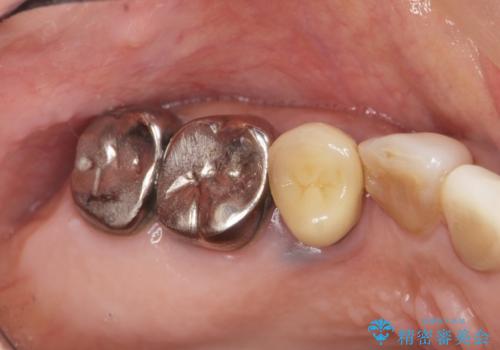

- ぐらぐらする小臼歯の治療を求めて来院されました。

X線検査、歯周組織検査より、歯は割れてしまい周囲の骨が高度に吸収してしまっている状態でした。

合わせて周囲の根尖病変や銀歯を治療するためにインプラントではなく、ご相談の上ブリッジ治療を行う治療計画としました。